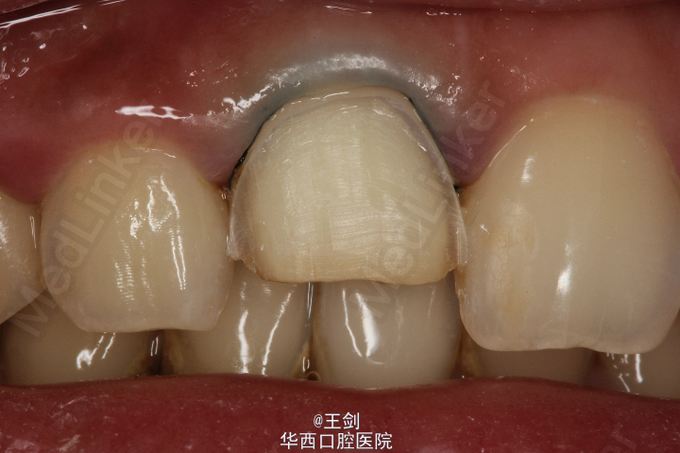

拟行CAD/CAM贴面修复11牙,当天备牙,当天戴牙

CAD/CAM 技术制作贴面可以达到高度密合,大大节省诊疗时间等优点